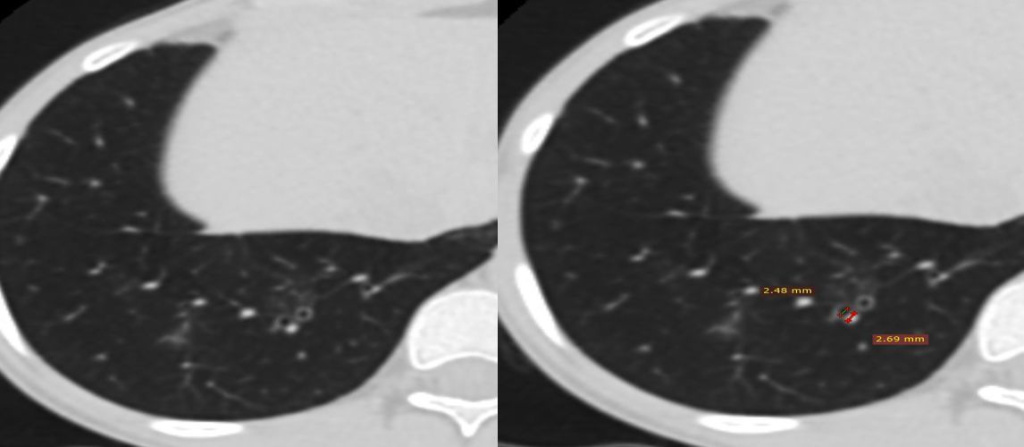

Своевременное выявление бронхоэктазов у детей имеет важное прогностическое значение, обусловлено возможной их обратимостью со временем при эффективном лечении, а также рядом существенных различий между бронхоэктазами с дебютом в детском возрасте и дебютом у взрослых, которые могут отражать разные фенотипы бронхоэктазов. У взрослых пациентов с бронхоэктазами, развившимися в детстве, течение патологического процесса более тяжелое и более худший прогноз по сравнению с бронхоэктазами, начавшимися во взрослом возрасте. Европейское респираторное общество в 2020 году предложило новую формулировку термина «бронхоэктаз» у детей и подростков, и в настоящее время под данным термином подразумевается аномальное расширение бронхов при компьютерной томографии (КТ) грудной клетки, которое при раннем обнаружении может быть обратимым. КТ является в настоящее время «золотым стандартом» для подтверждения бронхоэктазов у детей и подростков. Данный метод входит в минимальный набор тестов для детей и подростков с подозрением на бронхоэктазы согласно рекомендациям Европейского респираторного общества. При проведении КТ рекомендовано выполнение непрерывного спирального сканирования с коллимацией 1 мм, исследование проводится без внутривенного контрастирования с возможностью применения низкодозовых протоколов. Для оценки состояния бронхов у детей и подростков необходимо использовать педиатрические критерии бронхо-артериального соотношения (> 0,8).

В обзоре литературы, посвященном данной проблеме который был подготовлен главным врачом Международного медицинского центра Балтмед (ех-Finemedic) Гаврилова Павла Владимировича и опубликован в журнале Радиология – практика (ВАК) проиллюстрированы особенности визуализации бронхоэктазов у детей в контексте рекомендаций Европейского респираторного общества.

Гаврилов П.В. Лучевая визуализация бронхоэктазов у детей и подростков (обзор литературы с собственными наблюдениями). Радиология – практика. 2021;(5):115-128.